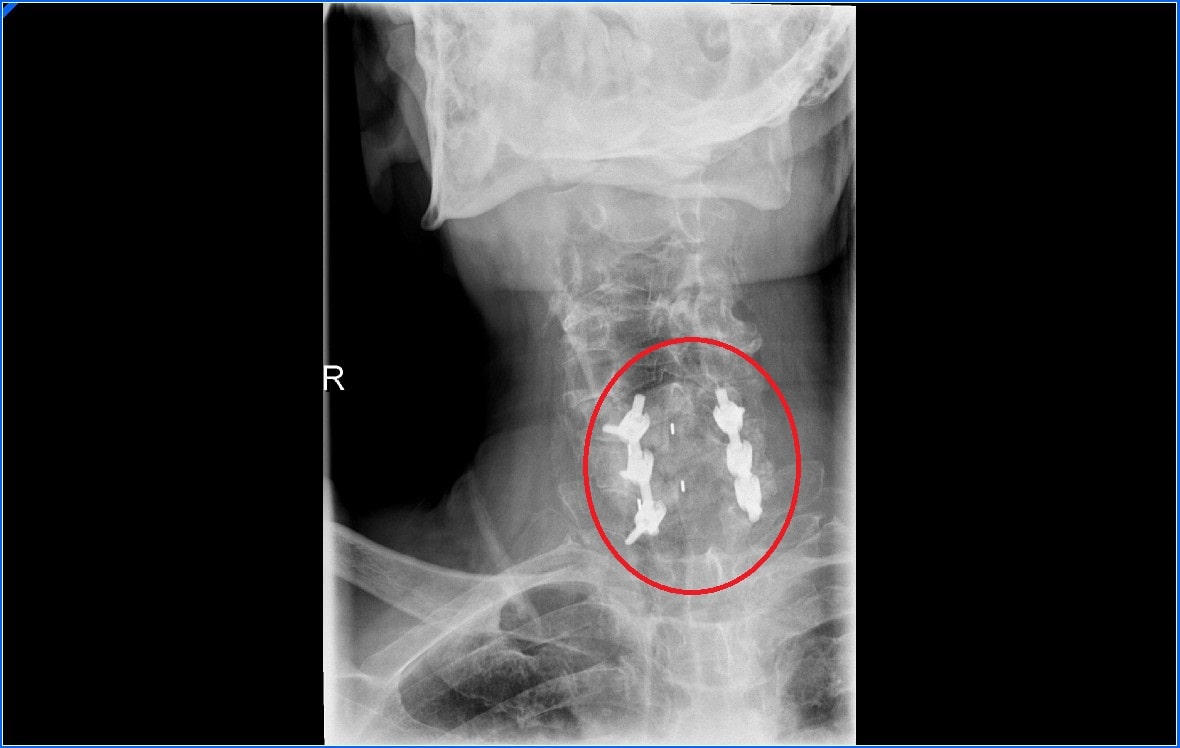

Existen distintos sistemas para sustituir el disco intervertebral, podemos usar cajas intersomáticas, que son unas cajas que se ponen entre los cuerpos vertebrales. Estas cajas pueden estar realizadas de peek que es un polímero de plástico o de metal.

Además de las cajas para evitar que se mueva muchas veces hay que poner una placa con tornillos. En los últimos años se han desarrollado cajas que se pueden atornillar directamente a las vértebras.

La artrodesis cervical posterior no requiere quitar el disco intervertebral, para realizar la fusión vertebral usaremos tornillos y barras.